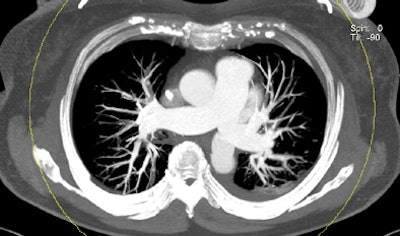

| Patient with bilateral segmental and subsegmental PE and large perfusion defects on dual-energy iodine distribution maps. All images courtesy of Dr. Ralf Bauer. |